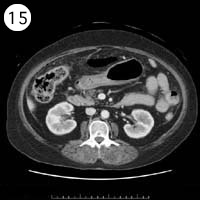

57歳 女性

単純CT

造影CT